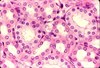

What type of tissue and class is this? What are its characteristics? Where is it located?

Type: Connective, blood

Description: RBC and WBC in plasma matrix

Location: Blood vessels (Gas, nutrient, waste transport)